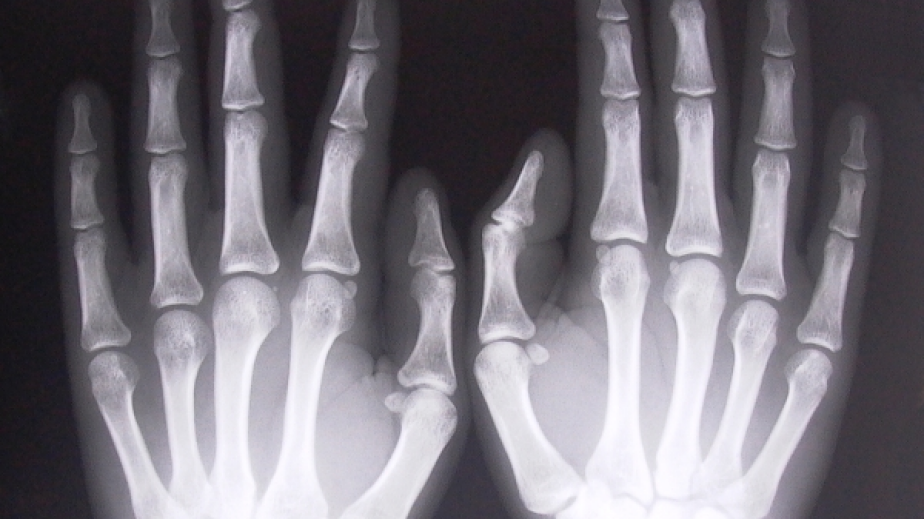

Скрининг на костната плътност ще прави Регионалната здравна инспекция в Перник. Стойността на изследването е само 5 лв. Кампанията е по повод Световния ден за борба с остеопорозата. Скринингът ще се извършва в сградата на инспекцията. Желаещите да се изследват могат да се запишат на тел. 0885052502.Кампанията се организира и провежда от Асоциация „Жени без остеопороза” - член на Международната фондация по остеопороза, в партньорство с Министерство на здравеопазването и Регионалните здравни инспекции, както и с ръководствата на общинските администрации. Тази тя е под мотото „Обичайте своите кости!”. Основната цел на кампанията е да се информира населението в Пернишко за остеопорозата като социално явление, като се акцентира върху ролята на активната профилактика на заболяването.Специалистите припомнят, че рискът от това заболяване е по-висок при жените след 40-годишна възраст. Според тях храната е първото и основно лекарство срещу остеопорозата. Приемаме достатъчно калций и протеини заздравяват костите.